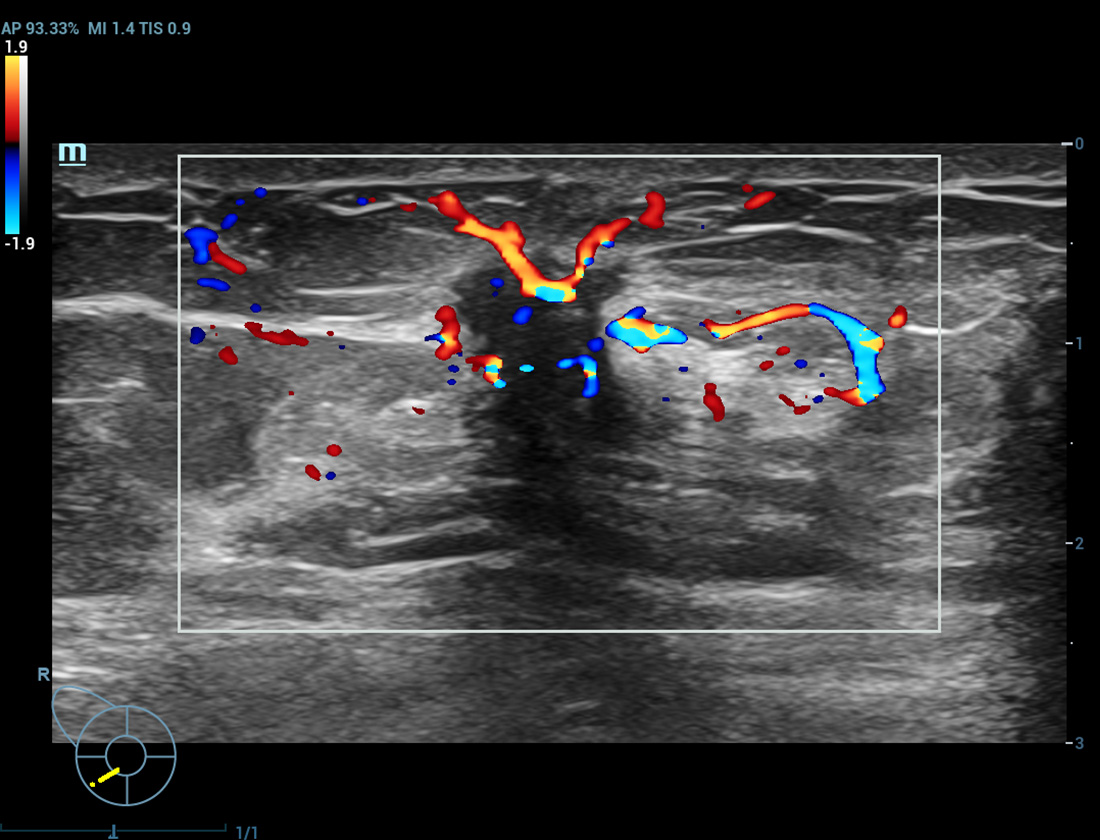

Angiografia ultramicroscû°pica (Ultra Micro Angiography, UMA)

UMA aumenta a confian?a diagnû°stica ao expandir a visibilidade dos fluxos sanguûÙneos atûˋ o nûÙvel de vasos minû¤sculos, com sensibilidade e resolu??o superiores.

sUMA ã Rins

pUMA ã Massa mamûÀria

sUMA ã C?ncer de tireoide

cUMA ã Massa mamûÀria

Massa mamûÀria

CEUS ã Massa mamûÀria